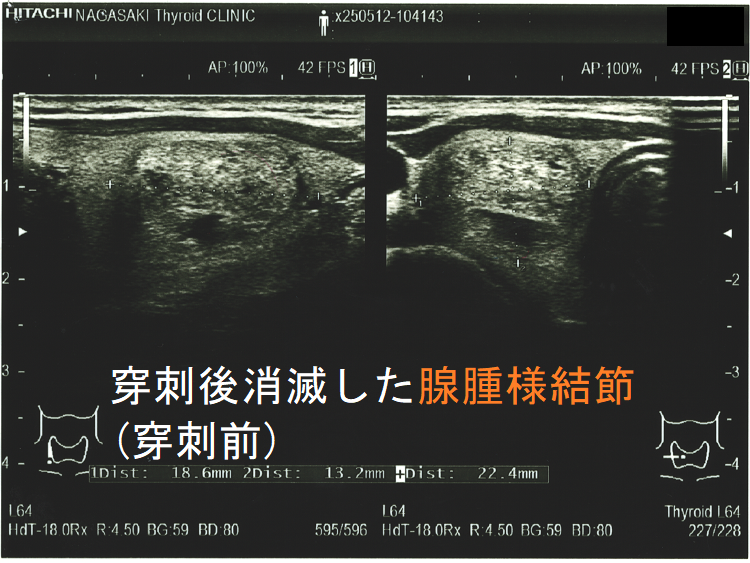

穿刺細胞診後内部融解

ケース①

ケース②